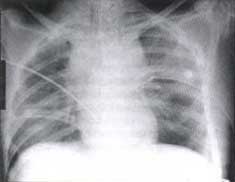

Figura No. 5. Radiografía de control de la misma paciente una hora más tarde

Luego de colocar los tubos de toracostomía. Se observa aumento importante del ensanchamiento mediastinal que habla de lesión vascular.